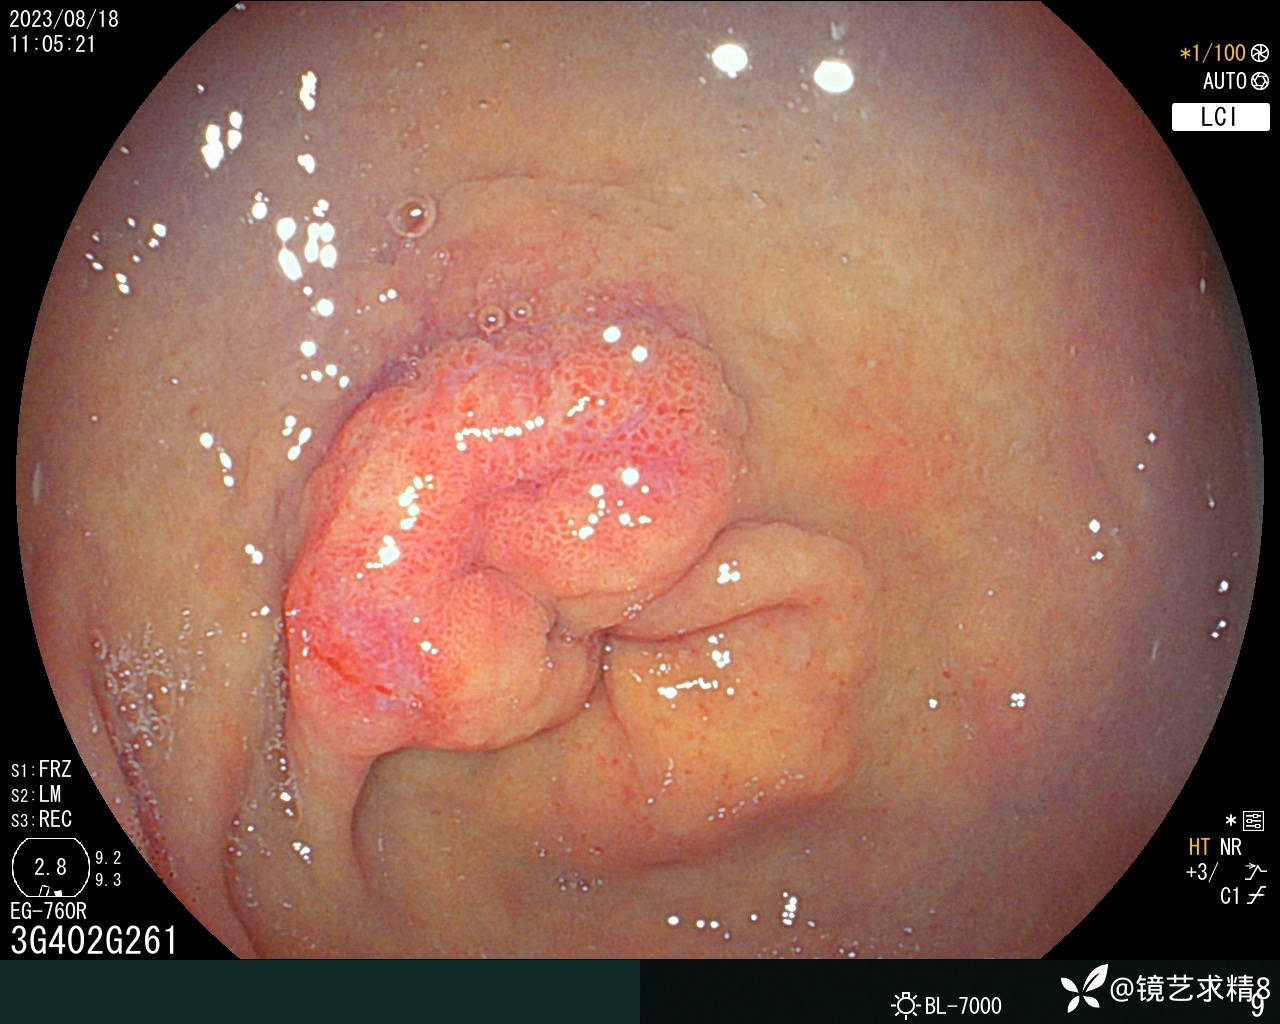

胃窦:黏膜红白相间,前壁与小弯侧交界近幽门见一0-Ia+IIc型病变,约20*30mm大小,BLI染色局部呈淡茶色,边界可见,表面结构欠规则,取病检2块+HP检查,质软。

内镜下诊断:1. 胃窦0-Ia+Ic型病变,不除外早期ca?请结合病检+HP检查